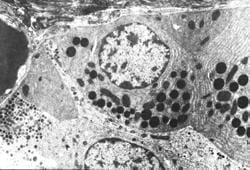

Figura (M/E x3500). Se observan gránulos de zimógenos redondos, grandes y electrón densos en células endocrinas acinares pancreáticas y gránulos neurosecretores pequeños de naturaleza endocrina (Fernández MO, Vivanco A y Domínguez C. Nesidioblastosis del páncreas: presentación de dos casos estudiados al microscopio electrónico (en el Hospital Pediátrico Cerro, de La Habana). VI Congreso Virtual Hispanoamericano de Anatomía Patológica. https://conganat.uninet.edu/6CVHAP/autores/trabajos/T237/index.html